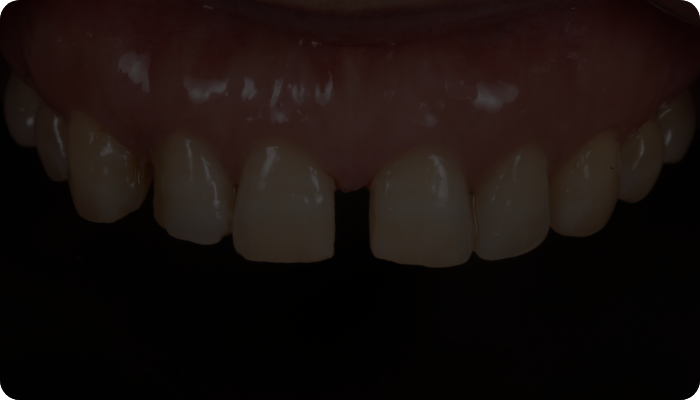

얇고 투명한 투과율로 높은 심미성, 높은 강도를 자랑하는 리튬 다이 실리케이트 블럭을

이용하여 적은 치아 삭제로 이상적인 치아를 복원이 가능합니다.

두꺼울수록 치아 삭제량이 많아지는 기존의 방식을 보완한

매우 얇고 치아에 잘 맞는 0.1mm 두께 보철로 자연스러운 라미네이트를 진행합니다.